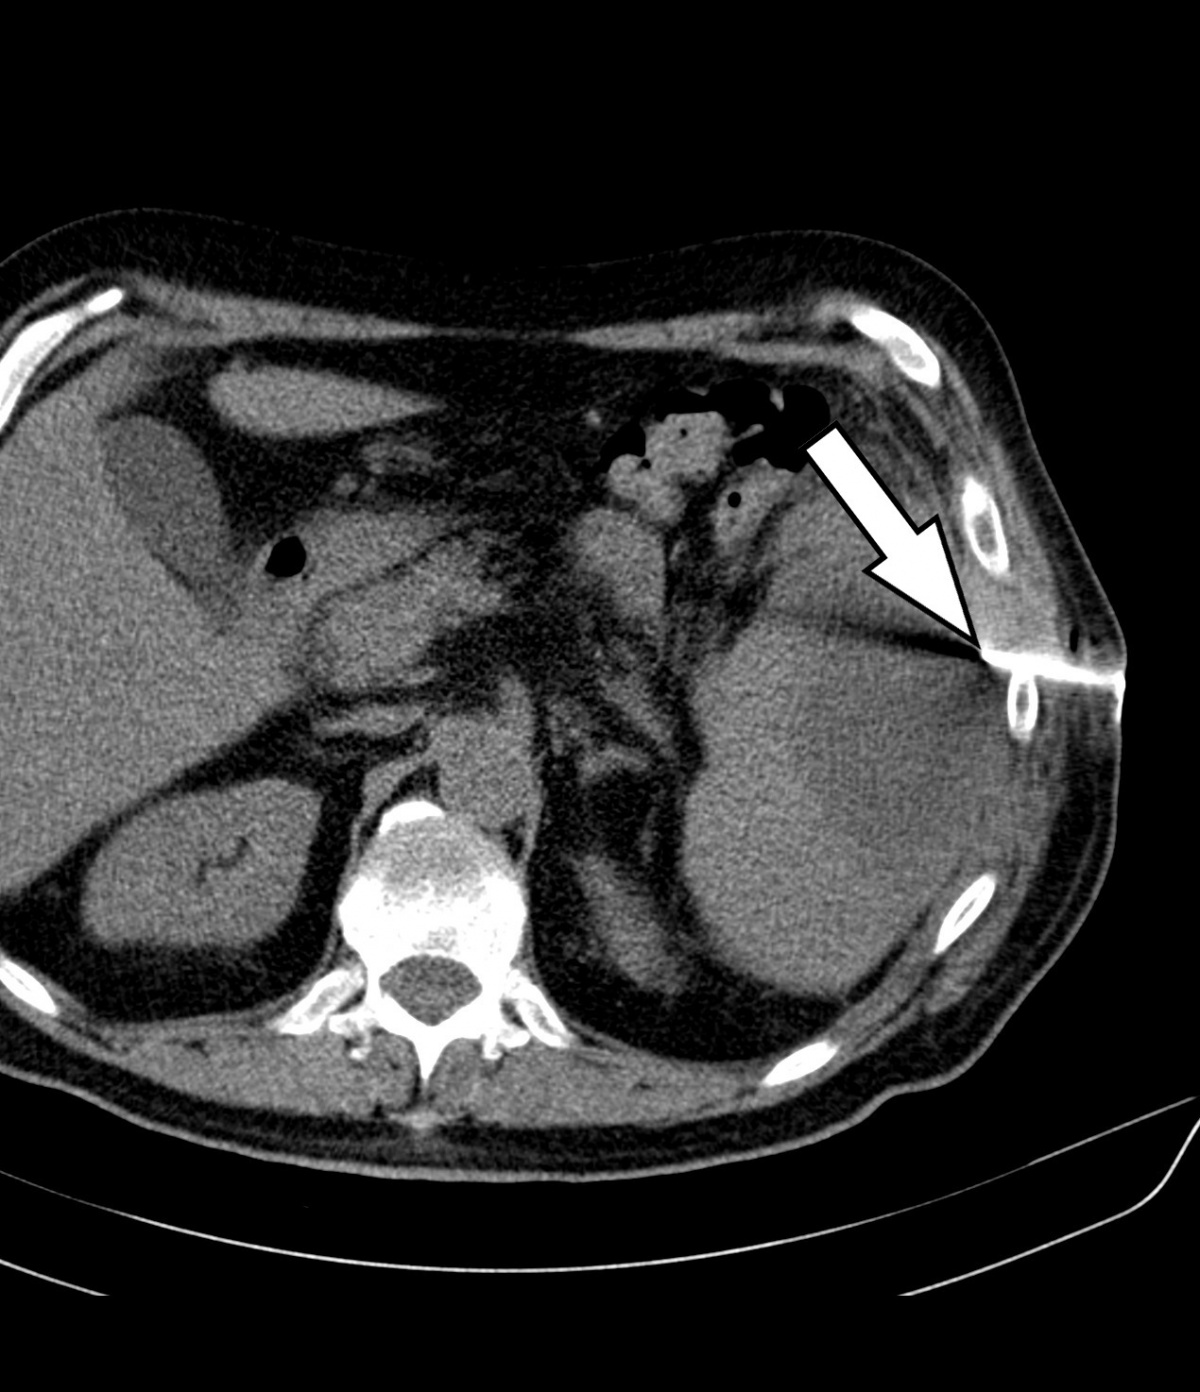

sich die regelgerecht einliegende Drainage (Pfeil). Der Abszess

konnte vollständig entleert werden.

Als weiterführende Diagnostik erfolgte unmittelbar im Anschluss eine kontrastmittelverstärkte CT des Abdomens -[Philips® -Ingenuity 64 x 0,625 mm, SD 5 mm, KI 5 mm, Pitch: 1,142; KM Dosis 100 ml/Ultravist300®, Flussrate 3 ml/sec]. In der Milz zeigte sich eine 9 x 8 x 6 cm große, zentral hypodense (25 HE¹) Raumforderung mit randständig teils inhomogener überwiegend linearer Kotrastmittelaufnahme, eine Imbibierung des umliegenden Fettgewebes und eine Verdickung des Retroperitoneums – insgesamt passend zu einem Abszess (Abbildung 1). Auf genaueres Befragen gab der Patient an, 3 Monate zuvor beim Sturz auf einen Baumstamm ein links-abdominelles Anpralltrauma erlitten zu haben. So folgerten wir, dass es im Rahmen dieses Traumas zu einem Milzhämatom und im weiteren Verlauf zu dessen Superinfektion mit Abszedierung gekommen war.

Im interdisziplinären Konsens erfolgte noch am selben Tag die interventionelle Therapie mittels CT-gestützter Drainageneinlage. In Rückenlage wurde nach Lokalanästhesie unter sterilen Kautelen in Seldinger-Technik CT-gesteuert ein 12F-Pigtailkatheter implantiert (Abbildung 2). Hierbei entleerten sich 240 ml einer eitrig-trüben übelriechenden Flüssigkeit. Proben zur mikrobiologischen Diagnostik wurden asserviert. In der abschließenden computertomografischen Lagekontrolle zeigte sich der Milzabszess vollständig entleert und kollabiert (Abbildung 3).

In einer abschließenden CT (7 Tage nach Drainageeinlage) bestätigte sich die vollständige Entleerung und Kollabierung der Abszesshöhle (Abbildung 4). Somit konnte eine erfolgreiche definitive Behandlung des Milzabszesses konstatiert und die Drainage entfernt werden. Die Indikation zur Befundkontrolle mittels CT wurde gestellt, da der subphrenische Raum sonografisch oft schwierig und nur unzureichend einsehbar ist.